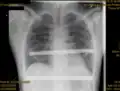

Pectus excavatum on PA chest radiograph with shift of heart shadow to the left and radioopacity of the right paracardiac lung field

Chest x-rays are also useful in the diagnosis. The chest x-ray in pectus excavatum can show an opacity in the right lung area that can be mistaken for an infiltrate (such as that seen with pneumonia).[23] Some studies also suggest that the Haller index can be calculated based on chest x-ray as opposed to CT scanning in individuals who have no limitation in their function.[24]